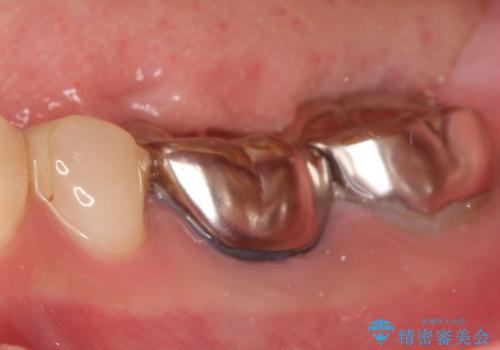

【メタルフリー】オールセラミッククラウン

- 金属冠を白くしたいことを主訴に来院されました。

オールセラミッククラウン(st)にて修復しております。

根管治療も合わせて行なっているため、期間がかかっております。